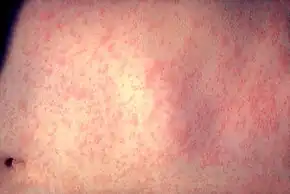

| A child showing a day-four measles rash | |

The characteristic measles rash is classically described as a generalized red maculopapular rash that begins several days after the fever starts. It starts on the back of the ears and, after a few hours, spreads to the head and neck before spreading to cover most of the body. The measles rash appears two to four days after the initial symptoms and lasts for up to eight days. The rash is said to "stain", changing color from red to dark brown, before disappearing.[32] Overall, measles usually resolves after about three weeks.[29]

A Filipino baby with measles